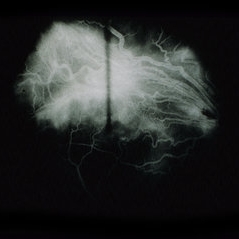

30 year old woman with confirmed von Hippel-Lindau disease. Her left eye was lost to large retinal angiomas, retinal detachment, and phthisis. She has a history of multiple cerebellar, brain stem, and spinal angiomas. The patient first developed a small retinal angioma along her inferotemporal arcade in the right eye in 1988. This was photocoagulated uneventfully. A picture of her normal right macula from January 15, 1991, is enclosed.